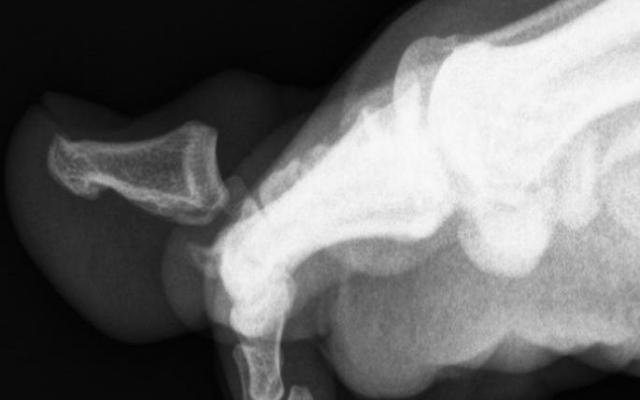

Een 20-jarige student presenteerde zich op de Spoedeisende Hulp met een pijnlijke, gezwollen grote teen links met hyperextensie in het interfalangeale gewricht, sinds een medestudent de voorgaande nacht op zijn voet was gaan staan. Bij lichamelijk onderzoek vonden wij een luxatie van de hallux en een excoriatie plantair. Anteroposterieure en laterale röntgenfoto’s toonden een luxatie naar dorsaal van de distale falanx van digitus I met interpositie van het sesamoïdbeentje. Onder lokale anesthesie volgens Oberst was het niet mogelijk de distale falanx te reponeren. Onder algehele anesthesie poogden wij op de operatiekamer onder doorlichting opnieuw gesloten te reponeren. Omdat dit…